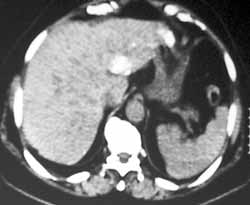

Рис. 1. Рак печени. (Слева) При КТ органов брюшной полости до химиоэмболизации  во II сегменте нечётко определяется патологический очаг размером до 2,0 см. (Справа) После введения масляных химиоэмболов денситометрическая плотность образования резко увеличилось.